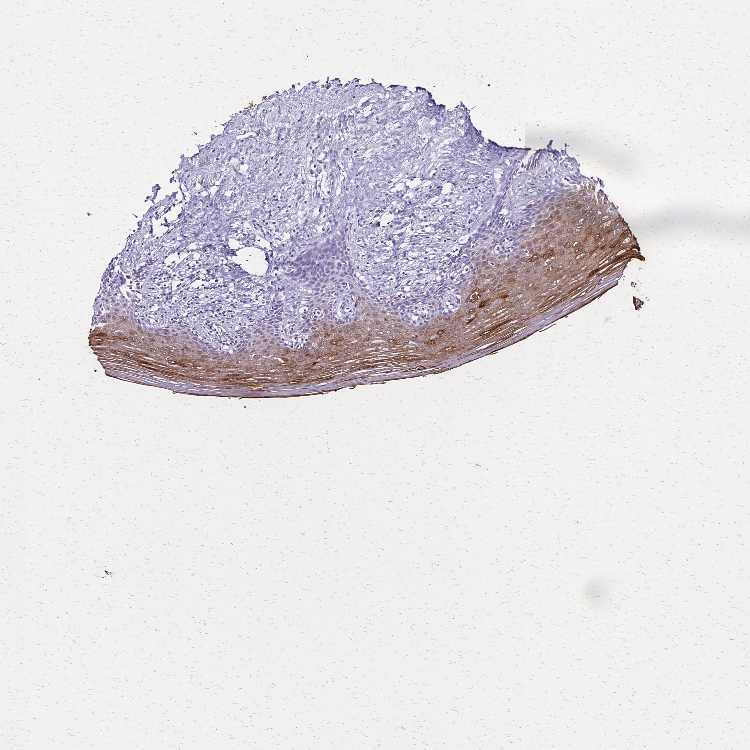

VAGINA - Antibody stainingi

Antibody staining in the annotated cell types in the current human tissue is reported as not detected, low, medium, or high, based on conventional immunohistochemistry profiling in selected tissues. This score is based on the combination of the staining intensity and fraction of stained cells.

Each image is clickable and will lead to virtual microscopy that enables deeper exploration of all samples and also displays staining intensity scores, fraction scores and subcellular localization as well as patient and tissue information for each sample.

Antibody CAB037321

Squamous epithelial cells High